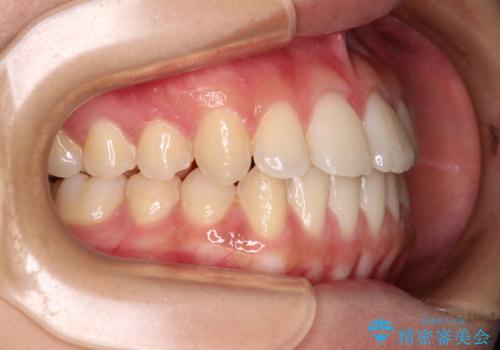

- 上下のデコボコと奥歯の咬みにくさを気にして来院された患者様です。

上顎骨の幅が下顎骨よりも小さく受け口傾向であったため、拡大装置により上顎骨の骨幅を広げて上下関係を改善し、その後インビザラインにて歯並びを整えることとしました。

下顎歯列は上顎歯列内に収まるように並んでいますが、上顎骨の幅が狭いと、下顎臼歯が全体的に舌側に傾斜した歯列となってしまいます。

舌側に傾斜した歯列は奥歯に力の負担がかかりやすく、歯磨きがしにくいなどの問題があるため、上顎骨拡大により舌側傾斜を改善することが可能となります。